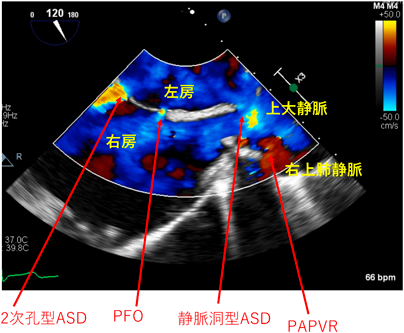

Fig. 4 72歳男性(ASD, PAPVR患者)の前立腺癌に対するロボット支援手術中の経食道エコー

術中経食道エコーでASD血流が右左方向になることがないことを確認しながら手術を行った.術前右心カテーテル検査RAP 2 mmHg, mPAWP 10 mmHg, PAP 30/8/15 mmHg, Qp/Qs 14.1/5.97 L/min, PVR 0.6 WU.運動負荷検査でSpO2低下なし.術中PAP 54/18/31 mmHg CVP 9 mmHgまで上昇. 抜管後PAP 25/10/17 mmHg CVP 4 mmHgに改善.mPAWP, mean pulmonary arterial wedge pressure; PAP, pulmonary arterial pressure; PAPVR, partial anomalous pulmonary venous return; PVR, pulmonary vascular resistance; Qp/Qs, 肺体血流比; RAP, right atrial pressure.